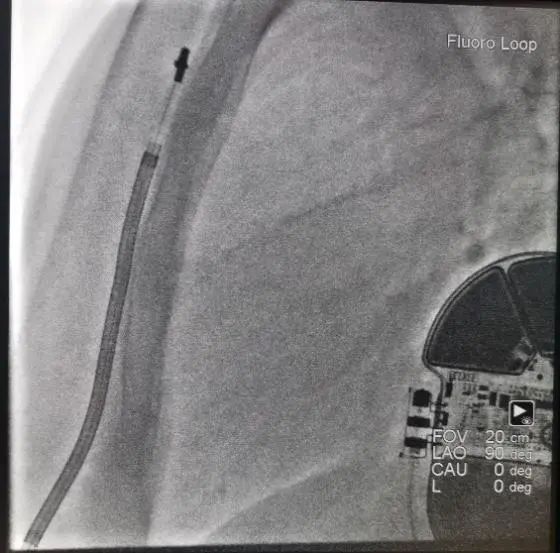

左心耳封堵术

患者术前心电监护示房颤心律,穿刺左侧股静脉1次,经6F静脉鞘送“电生理电极导管(四极)”至右室心尖部行右心导管检查,穿刺右侧颈内静脉一次,置入6F静脉鞘,沿鞘送“电生理诊断导管(十极)”至CS,穿刺右侧股静脉2次,分别置8.5F房间隔穿刺鞘,分别使用“一次性使用房间隔穿刺针”成功穿刺房间隔成功后将房间隔穿刺鞘置入左房,分别置入“星型磁电双定位标测导管”和“诊断/消融可调弯头端导管”。Carto3 三维标测系统指导下构建左房三维电解剖图。然后按以下步骤消融:在离右侧肺静脉口0.5cm处对右侧肺静脉进行环形消融,放电设置(50瓦,冷盐水流速30ml/min),各点时间10s左右,星型磁电双定位标测导管检测,肺静脉与心房达到双向电隔离为准;同样方法对左侧肺静脉进行环形消融,星型磁电双定位标测导管检测,肺静脉与心房达到双向电隔离为准。消融后给予200J同步电复律,患者转复为窦性心律。将其中一个8.5F房间隔穿刺鞘置换为心脏超声导管至左心房,将8.5F房间隔穿刺鞘置换为封堵器专用长鞘后将猪尾导管置入左房,调整至左心耳内,行左心耳造影,测量左心耳口部最大直径35mm,左房内无血栓,DSA指导下选用左心耳封堵器LAmbre3640,置入长鞘内,在左心耳内释放成功,造影检查提示封堵器位置良好,植入器械位置正确。造影检查提示未见明显分流,经心腔内超声可见植入器械位置正常,释放封堵器。结束手术,拔除电极及鞘管,局部加压止血,安返病房,术中生命体征平稳。